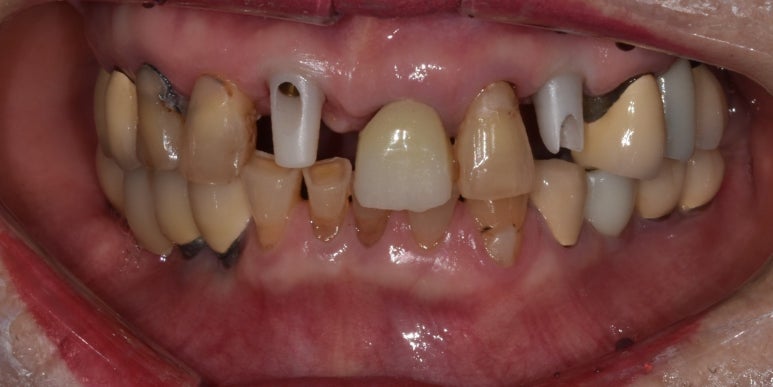

(좌) 앞니임플란트 시 지르코니아 어버트먼트를 장착한 상태

(우) 어버트먼트가 깨져 크라운과 함께 떨어진 상태

(좌) 2022-06-17 (우) 2023-02-04

지금 소개해드리는 환자분이 바로 이런 케이스였는데요.

앞니임플란트를 하셔서 금속으로 어버트먼트를 제작할 경우 색상이 비춰보일 수 있어

치아 색상과 유사한 지르코니아 어버트먼트를 하셨던 환자분입니다.

그런데 환자분께서 문에 부딪히는 바람에 이 어버트먼트가 깨져 크라운과 함께 탈락하고 말았습니다.

깨진 어버트먼트와 떨어진 크라운

일단 엑스레이를 촬영해보니 다행히도 임플란트 픽스처는 깨지지 않은 것으로 확인되었고,

픽스처가 뼈와 잘 유착되어 있는지 수치로 체크한 결과 이상이 없어서 1~2주 정도 지켜본 후

어버트먼트와 크라운만 다시 제작해 붙여드렸습니다.